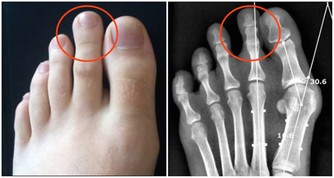

無需過分擔憂的眼表出血

醫學上又稱球結膜下出血,是因為眼球表面的球結膜血管破裂或其滲透性增加或眼部炎症造成出血。

眼表出血症狀

由於球結膜呈透明狀,所以出血後眼白部分可明顯看到一片鮮紅色,一般視力無影響,自覺症狀不明顯。

剛出血時呈鮮紅色或深紅色,時間長了就變成淡黃色,一般都能於幾天至幾週後慢慢吸收不留痕跡。